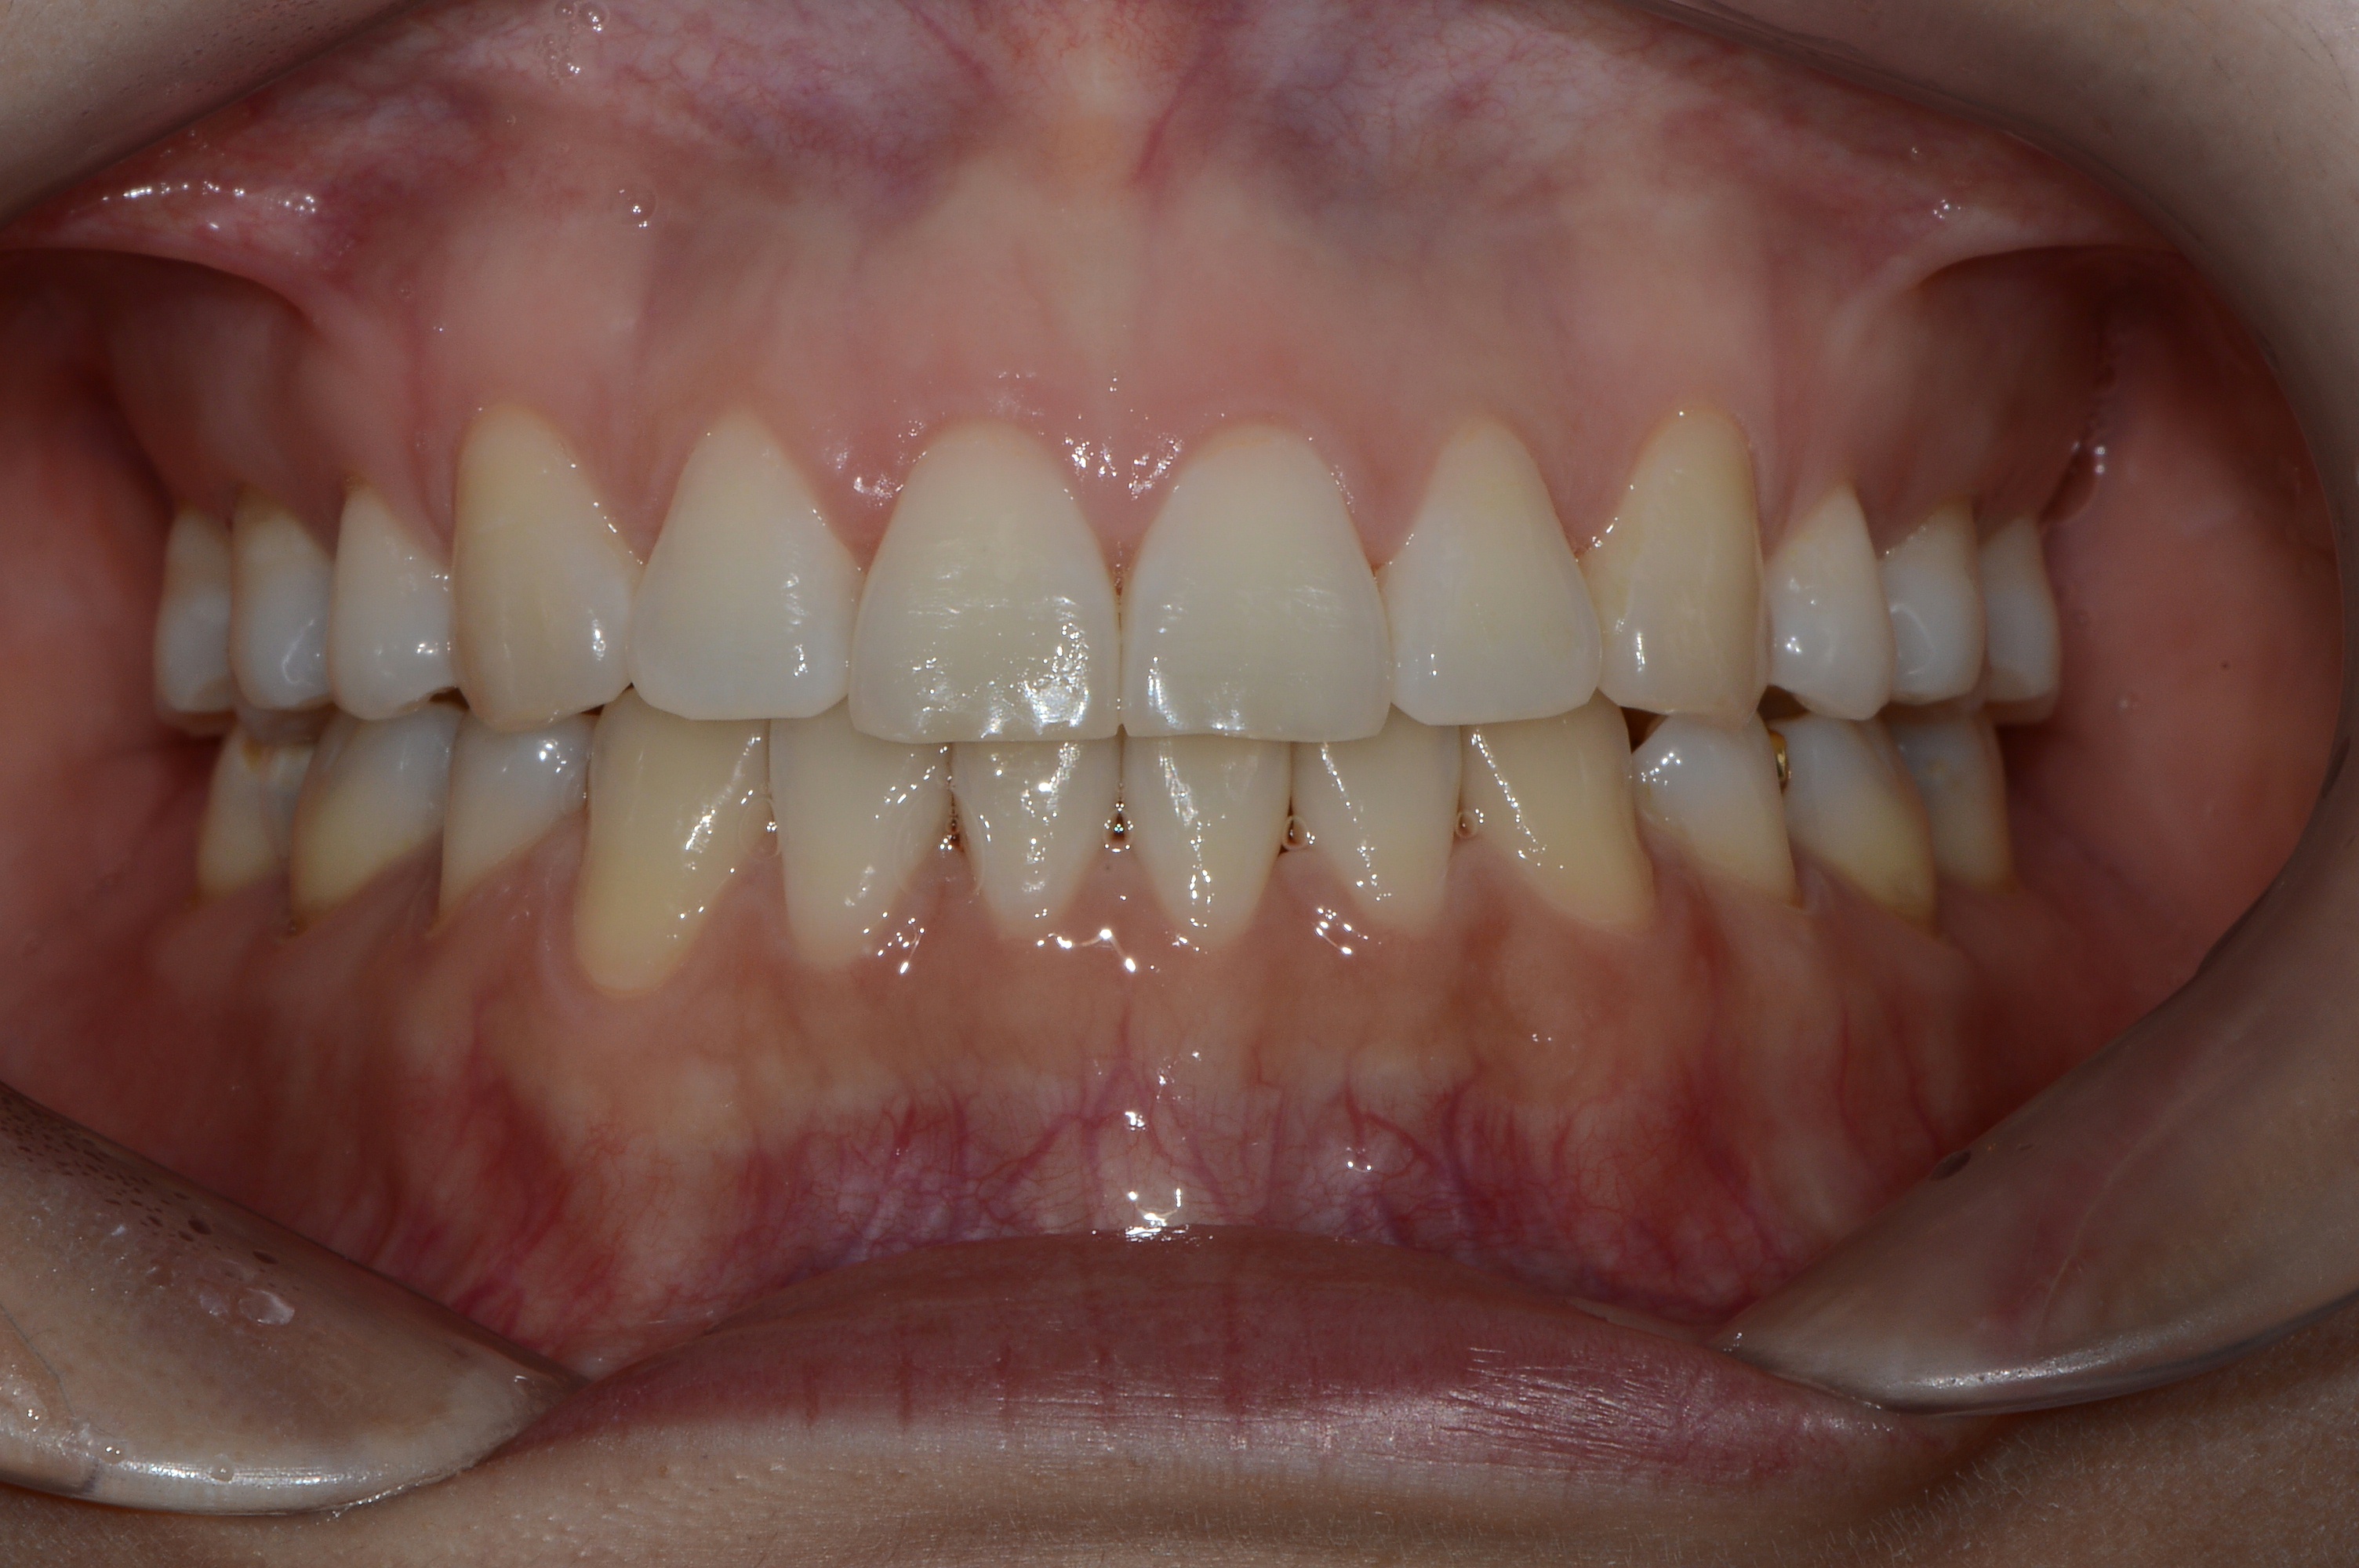

치료 후 사진입니다.